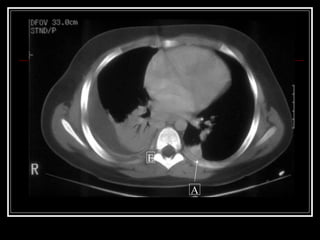

E A